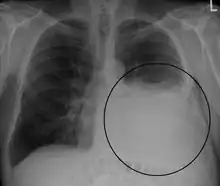

A pleural effusion appears as an area of whiteness on a standard posteroanterior chest X-ray.[14] Normally, the space between the visceral pleura and the parietal pleura cannot be seen. A pleural effusion infiltrates the space between these layers. Because the pleural effusion has a density similar to water, it can be seen on radiographs. Since the effusion has greater density than the rest of the lung, it gravitates towards the lower portions of the pleural cavity. The pleural effusion behaves according to basic fluid dynamics, conforming to the shape of pleural space, which is determined by the lung and chest wall. If the pleural space contains both air and fluid, then an air-fluid level that is horizontal will be present, instead of conforming to the lung space.[15] Chest radiographs in the lateral decubitus position (with the patient lying on the side of the pleural effusion) are more sensitive and can detect as little as 50 mL of fluid. Between 250 and 600mL of fluid must be present before upright chest X-rays can detect a pleural effusion (e.g., blunted costophrenic angles).[16]

Massive left-sided pleural effusion (whiteness) in a patient presenting with lung cancer.